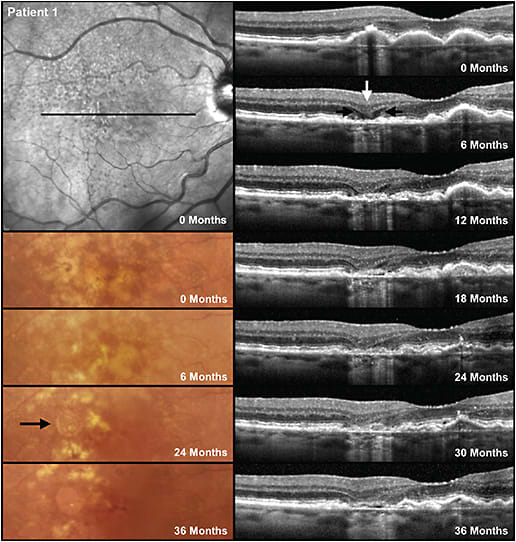

GJ: There has been confusion about distinguishing iRORA from nascent GA (nGA). This term was defined by Dr. Robyn Guymer’s group at the Centre for Eye Research Australia to describe signs that, when present, indicate a very high risk of progression to GA (Figure 2).4 The signs needed for nGA are the subsidence of the outer plexiform layer and inner nuclear layer, or a hyperreflective wedge-shaped lesion in Henle’s nerve fiber layer. There was no requirement for the presence of hypertransmission or RPE changes, although they are often present. Dr. Guymer’s research finds nGA to be more robust as a risk factor for progression than signs of iRORA.

Most cases of nGA will satisfy the definition of iRORA and sometimes cRORA. However, if for example there is no hypertransmission due to debris on Bruch’s membrane that is blocking the signal, then nGA may be present but not iRORA or cRORA. There are cases of iRORA in which the photoreceptor signs are simply a loss of the ellipsoid zone or external limiting membrane or thinning of the outer nuclear layer but no subsidence or wedge, and as such those patients do not have nGA. The subsidence of the outer plexiform layer and inner nuclear layer seem to be a sign that the loss of the photoreceptors is more advanced. Given that it has been difficult for researchers and clinicians to agree on the status of the RPE that is required to determine the presence of iRORA and cRORA, and that it is easier to reproducibly identify nGA, nGA appears a more robust sign when looking for early signs of atrophy on OCT.